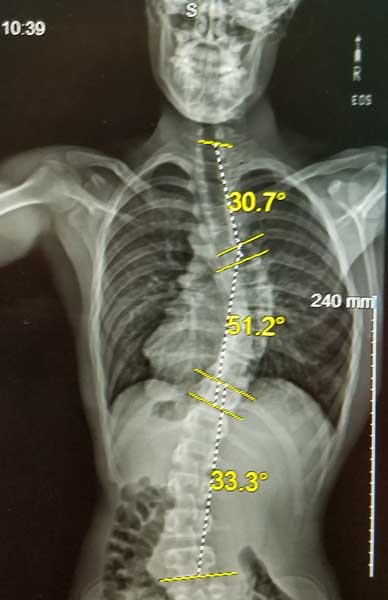

SCOLIOSIS

How Do I Know My Child has Scoliosis?

Signs of Scoliosis.